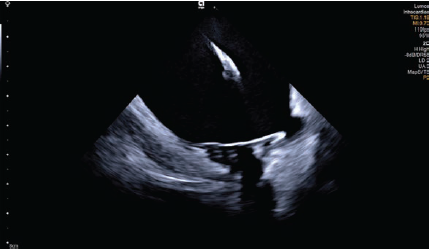

The catheter-based treatment known as pulsed-field ablation (PFA) is emerging as an innovative method of ablation for the treatment of atrial fibrillation. It creates precisely demarcated cardiac lesions that preserve tissue architecture; cell death is confirmed by histological evidence of electroporation, which uses electrical fields to increase cell permeability. PFA can be augmented via four-dimensional (4D) intracardiac echocardiography (ICE) to guide catheter placement, verify tissue contact, and evaluate lesion formation. Additionally, 4D ICE may help clinicians assess sufficient energy delivery to intended tissue and minimize the potential for hemolysis, or the rupturing of red blood cells. In this case, 4D ICE (AcuNav Lumos 4D ICE catheter, Siemens Healthineers) was used to perform PFA and provided detailed views of cardiac anatomy and visualization of tissue contact in multiple planes (Figures 1-2). AcuNav Lumos 4D ICE also guided the transseptal puncture and tenting with visualization of left atrial appendage in the far field (Figure 3) to confirm absence of thrombus.